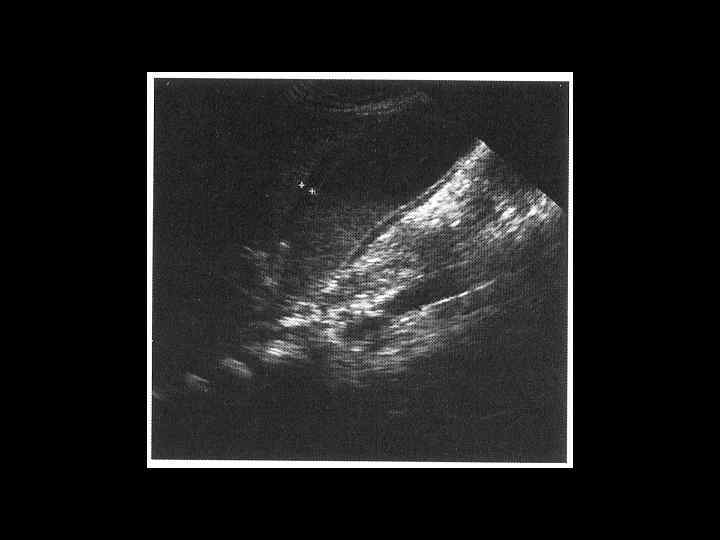

АКТУАЛЬНЫЕ ВОПРОСЫ РЕНТГЕНОЛОГИИ ЛУЧЕВАЯ ДИАГНОСТИКА ЗАБОЛЕВАНИЙ ЖЕЛЧЕВЫДЕЛИТЕЛЬНОЙ СИСТЕМЫ Желчекаменная болезнь УЗ семиотика